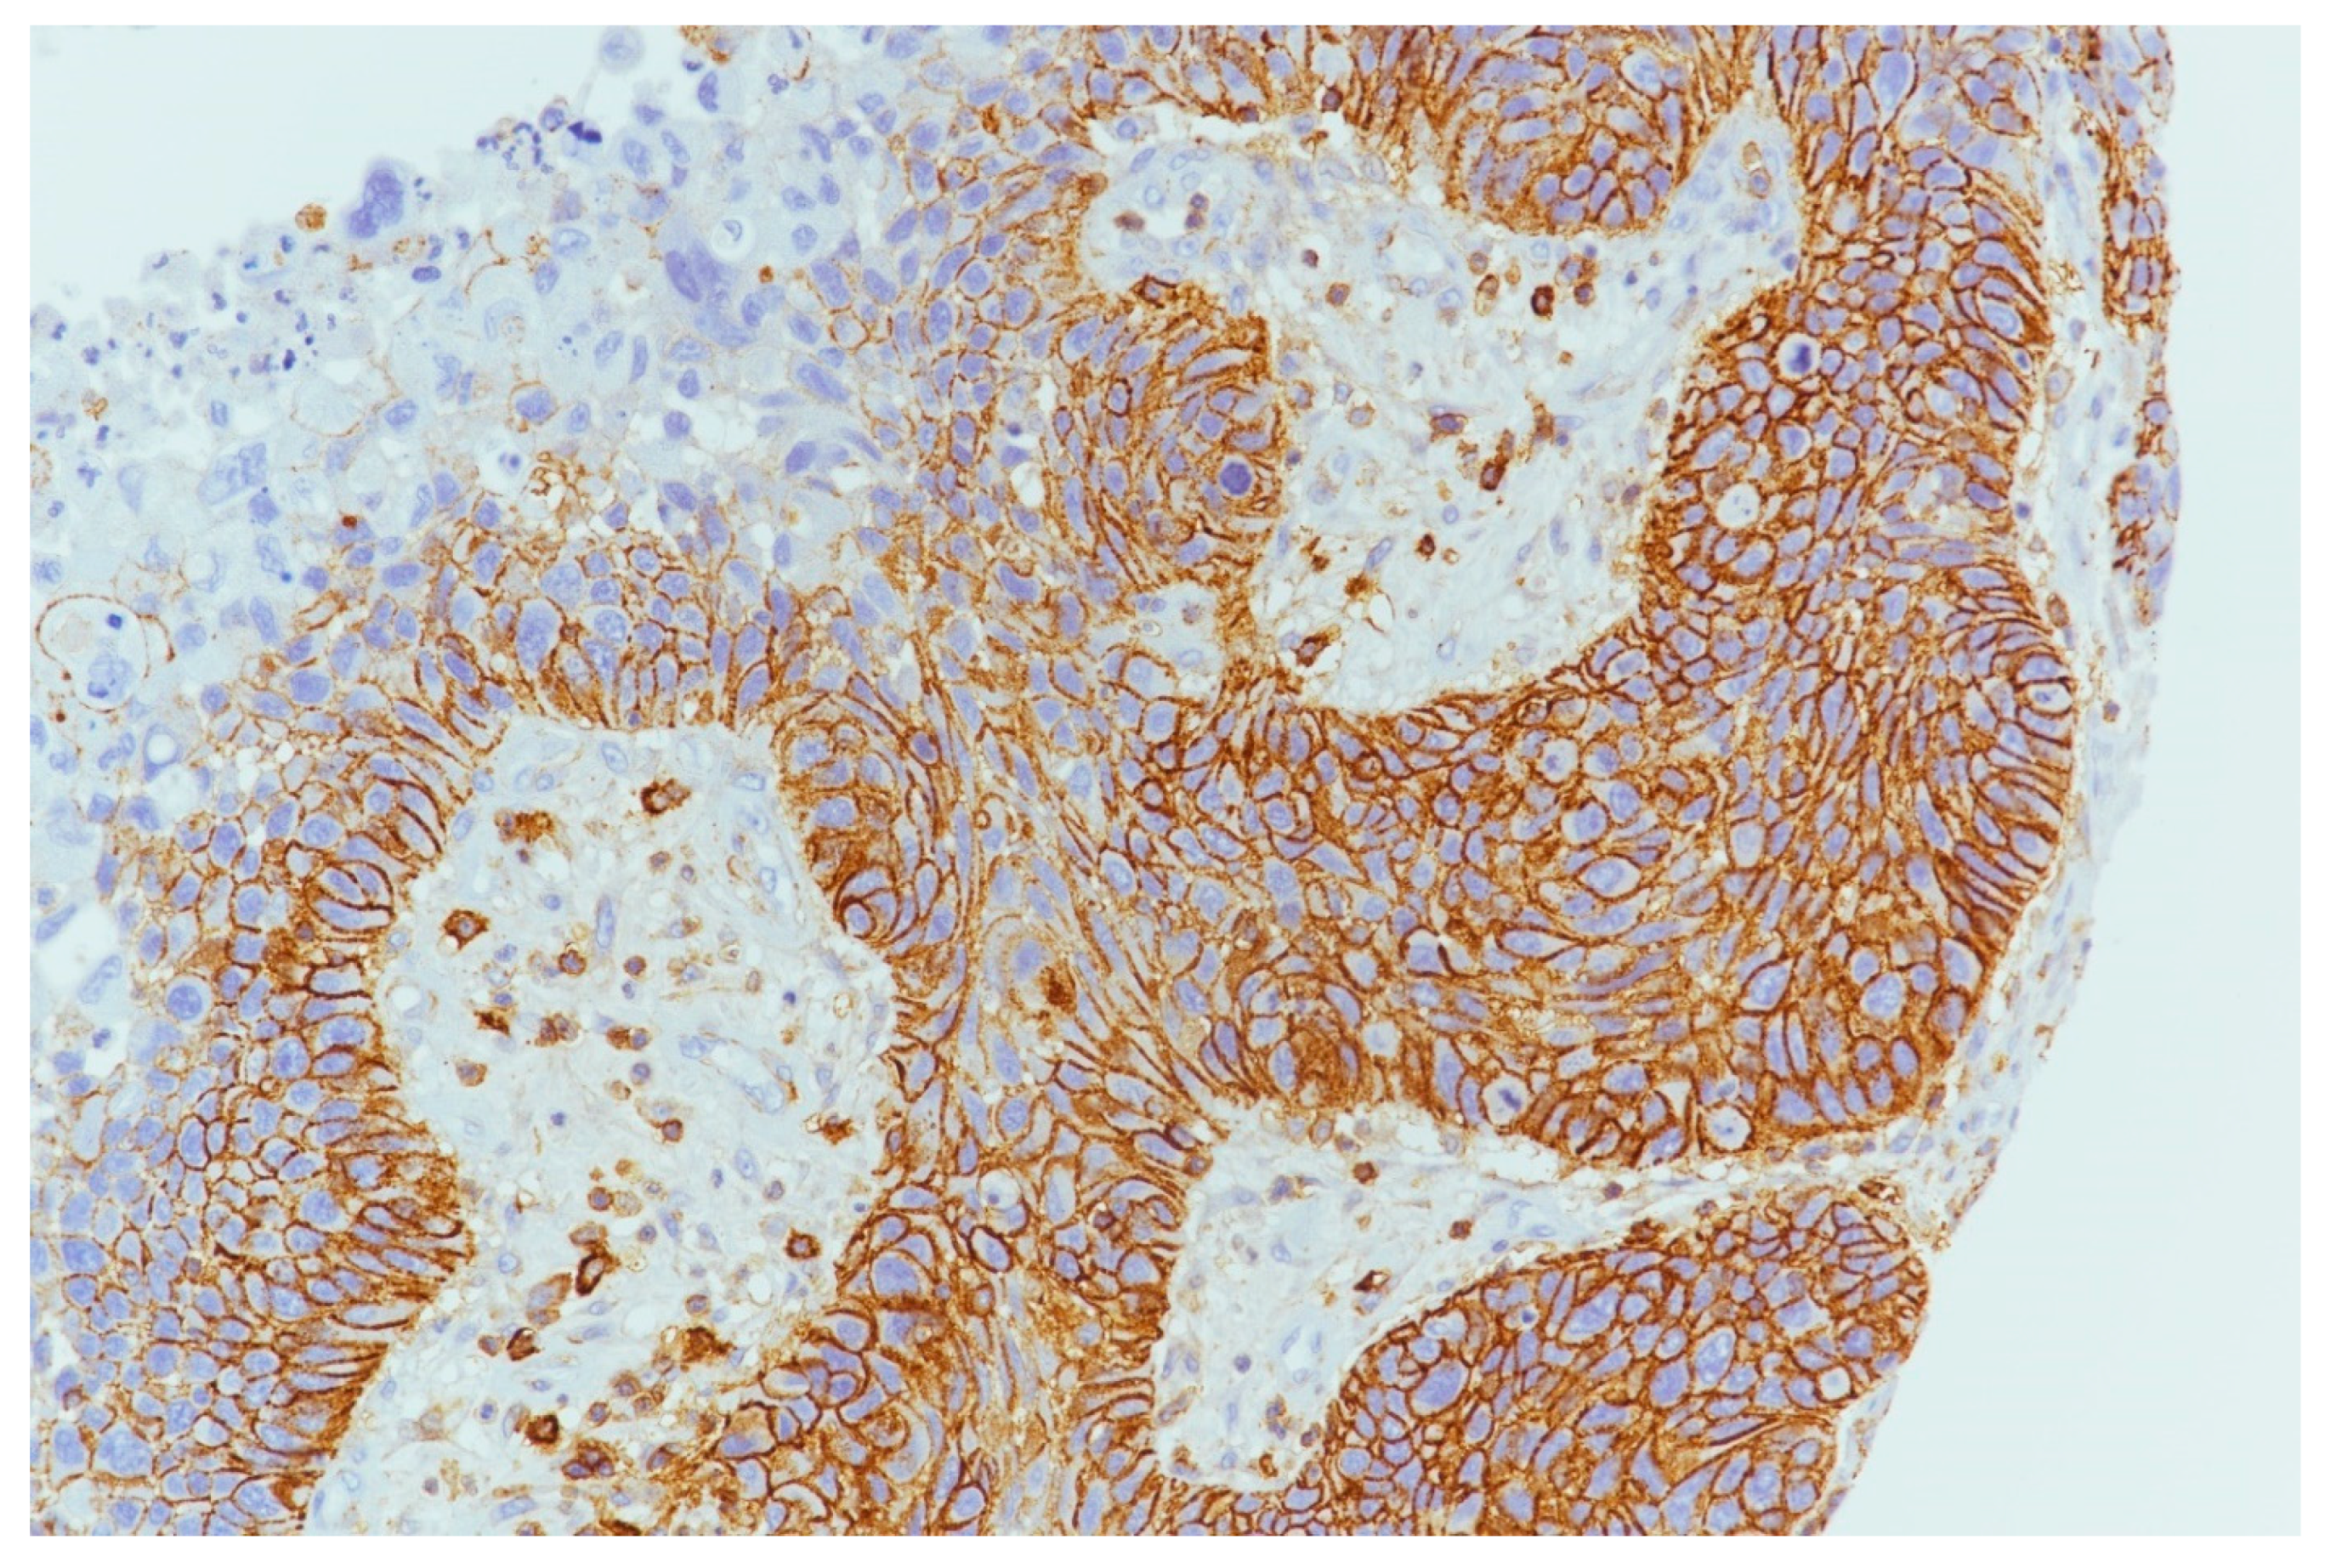

4.3. PDL1 Expression

4.4. ATG7 Expression

4.5. Correlation between the Expression of Biomarkers